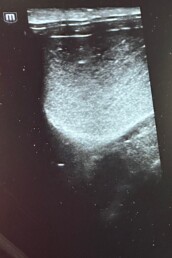

Weiterführende Untersuchungen: Ultraschall

- rektale Ultraschalluntersuchung der Blase

- auffälliges, abgesunkenes Sediment in der Harnblase/am Harnblasenhals

- ggr. Verdickung der Blasenwand